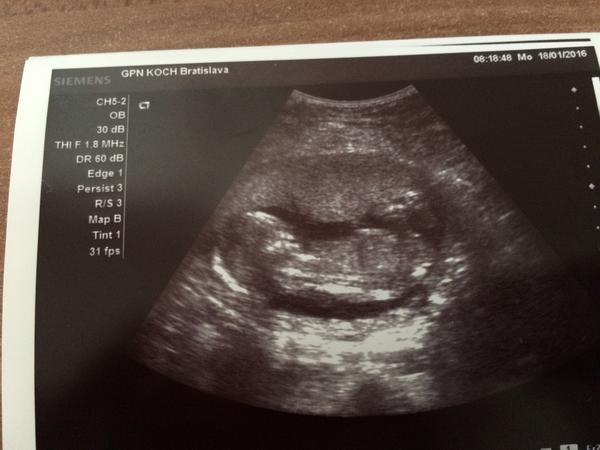

@nicolettka2126 vobec netusime ako sa bude volat 🙂, no lekar zapol sono, pomeral a hovori, kuknem este pohlavie a maly sups a nohy odseba 🙂 baby ja som spokojna, Viktorkovi hovori lekar budes mat braceka a Viktorko zacal ze Hura hura bracek. podla mna bol mimo z toho co videl 🙂 ale ja som stastna, chalana som chcela 😉